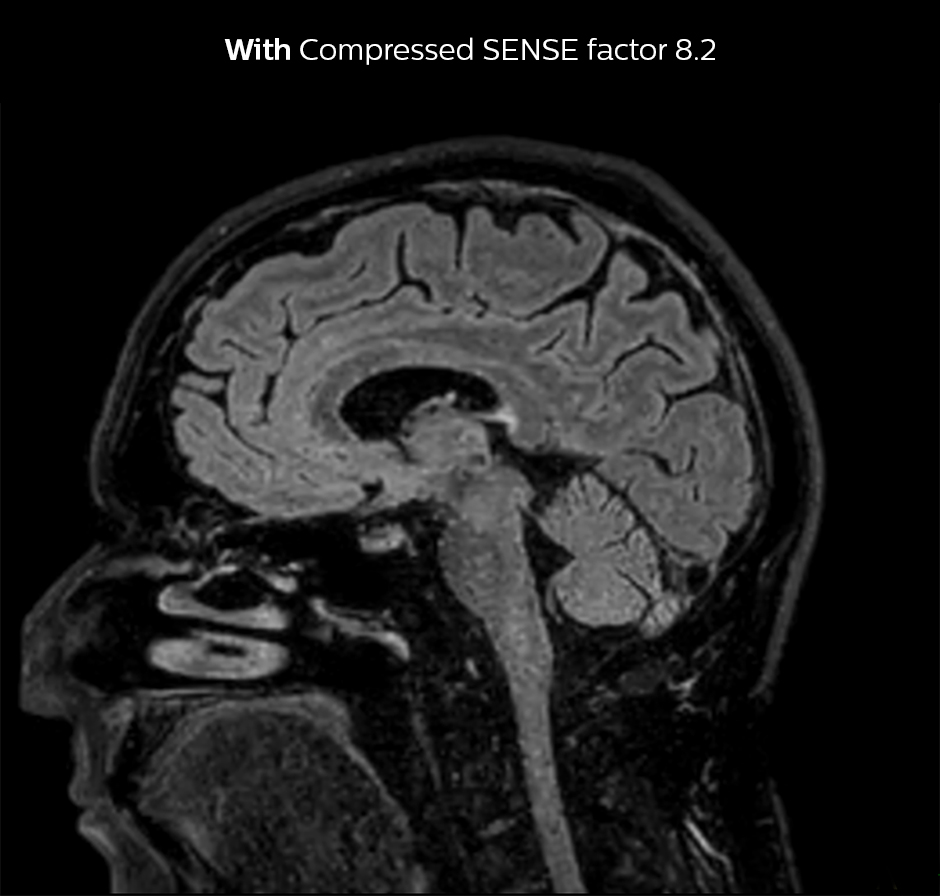

Shorter scan time in brain

Compressed SENSE allows 28% shorter scan time with the same spatial resolution.

3D FLAIR, scan time 5:02 min, voxel size 1.1 x 1.1 x 1.1 mm, Ingenia 1.5T.

3D FLAIR, scan time 3:36 min, voxel size 1.1 x 1.1 x 1.1 mm, Ingenia 1.5T.